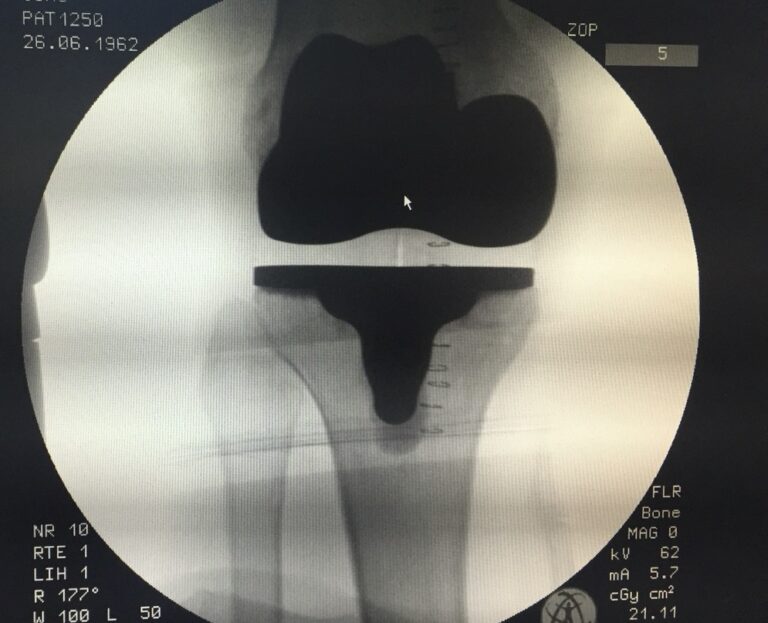

Πώς γίνεται – συνοπτικά

- MRI ή CT του γόνατος

- 3D ανάλυση & ψηφιακός σχεδιασμός

- Κατασκευή εξατομικευμένων οδηγών/εμφυτευμάτων

- Χειρουργείο με ακρίβεια βάσει του σχεδίου